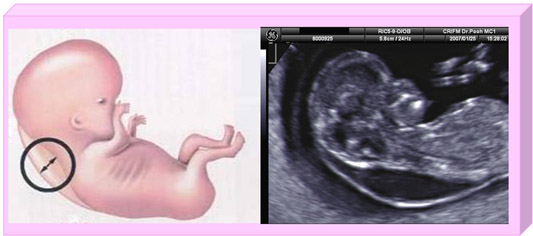

下図は、赤ちゃんの首のむくみ(NT)の説明図と実際のエコー写真です。この赤ちゃんは、11週で5.9mmのむくみがありましたが、健常児で、このあとむくみもほとんど認められなくなりました。(出典:クリフム夫律子マタニティクリニック)